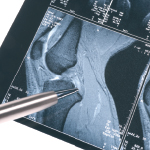

Centrum ortopedie a traumatologie je akreditované pracoviště MZČR. Zabývá se léčbou onemocnění velkých i malých kloubů a přednoží, léčbou úrazů a bolestí zad. Centrum využívá vysoce moderních operačních sálů uzpůsobených k provádění aseptických operací za využití nejmodernějších technologií. Ortopedické sály jsou plně digitalizované a napojené na PACS (digitální systém přenosu výsledků radiodiagnostických vyšetření). Páteří centra je artroskopická věž značky Smith & Nephew, C-rameno Ziehm Vision R a nejmodernější operační instrumentárium.

Lékaři centra jsou vyškoleni k provádění kloubních náhrad velkých kloubů nejmodernějšími metodami, včetně navigovaných výkonů, operací miniinvazivními přístupy či operací kolenního kloubu metodou Visionaire. Artroskopie a rekonstrukční výkony vazů jsou v centru každodenní rutinou.